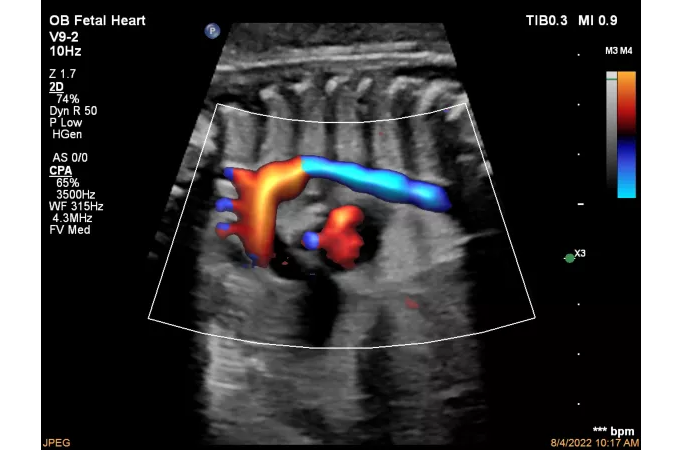

CPA дуги аорты плода с Flow Viewer

ЦДК сердца плода, четыре камеры, с Flow Viewer

CPA плаценты с Flow Viewer